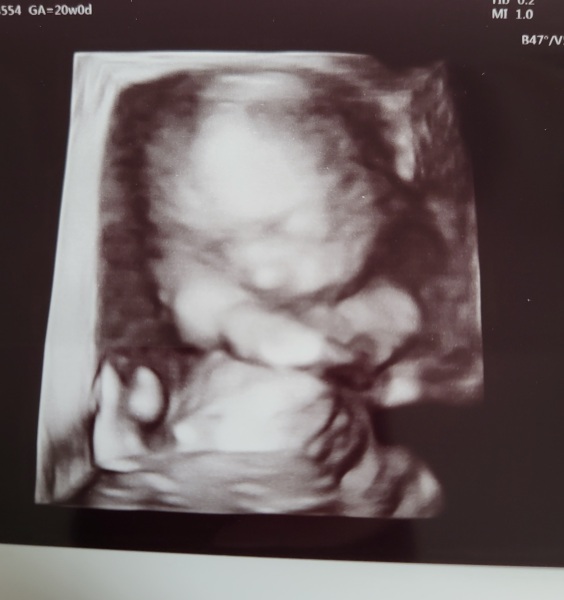

DiamondApricot · 23/06/2023 13:37

I am lucky enough to say that everything was fine for our baby girl this morning, only snag is that I have a low lying placenta. They're going to scan again at 34 weeks and it should move up by then but if not, I'm bound for a section.

@DiamondApricot what a lovely scan pic! I think the placenta etc has plenty time to move!

@DiamondApricot ahhh lovely little pic 😍 hopefully the placenta will move up as baby grows xx